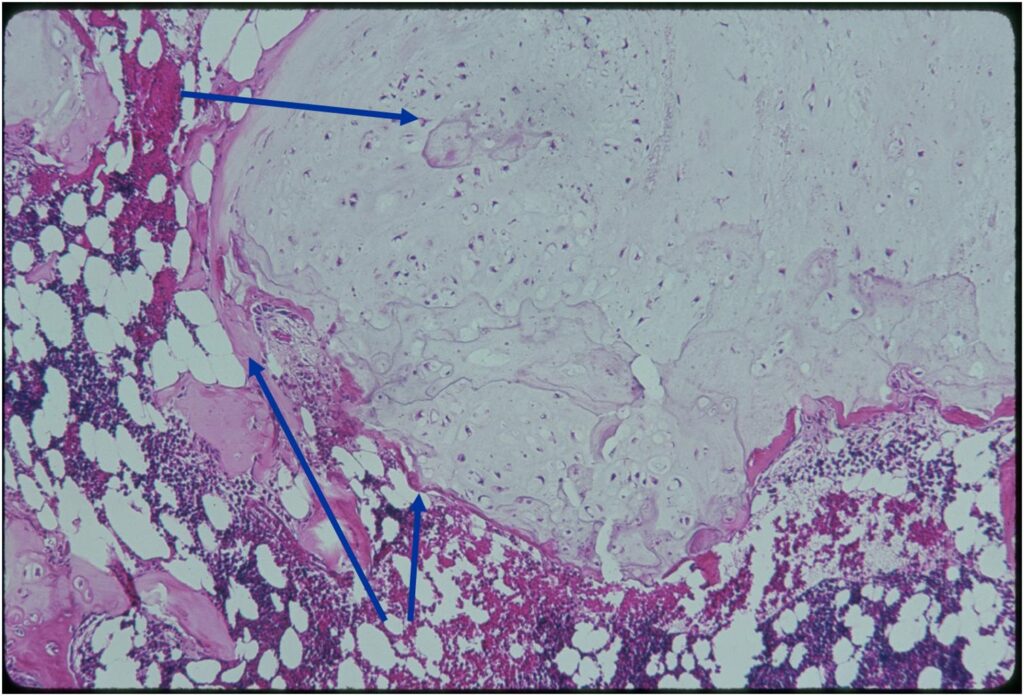

- Enchondromas are well defined lesions with cartilage arranged in lobules that are separated by fibrovascular septa

- Enchondral ossification may occur around periphery of lobules and when calcified appear as “Rings and Arcs” on X-rays

- Rests of hyaline cartilage with a lobular growth pattern

- The matrix has a ground glass basophilic appearance

- Variable amorphous calcification and enchondral ossification

- May cause mild expansile remodeling of bone and cortical thinning